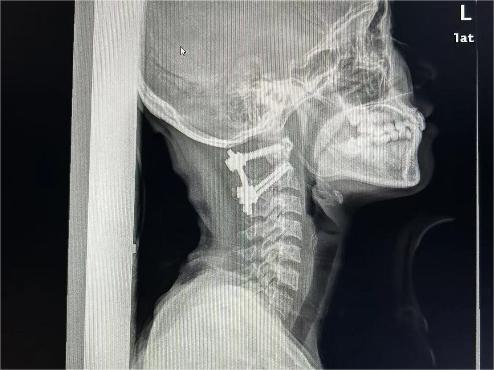

两个小时过去,疼痛不但没有缓解,还越来越厉害。她当即来到暨南大学附属第六医院(东莞市东部中心医院)脊柱外科就诊,做了颈椎X光后,结果令人大吃一惊:这不是简单的“落枕”,而是寰枢关节脱位III型。

寰枢关节脱位又称为寰枢椎脱位,是指颈椎的第一节(寰椎)、第二节(枢椎)之间的关节失去正常的对合关系。这是一种少见但严重的疾病,会引起延髓、高位颈脊髓受压,严重者致四肢瘫痪,甚至呼吸衰竭而死亡。

医生建议她马上住院治疗。入院后,主管医生立即帮她完善颈椎MRI,确认其寰枢椎脱位是由于横韧带断裂引起,予以枕颌带牵引治疗,恢复了寰枢关节正确解剖位置。同时,向上级医生汇报病情。

暨南大学附属第六医院(东莞市东部中心医院)副院长焦根龙博士是脊柱外科学科带头人,他查看了影像学资料、听取汇报后,判断晓娟应择期行手术治疗固定脱位的寰枢椎,不然可能再次脱位。

10月11日一早,在焦根龙带领下,手术室、麻醉科通力配合,全程实施神经电生理监测,脊柱外科团队成功为晓娟实施了寰枢椎脱位切开复位内固定植骨融合术,手术非常顺利,彻底消除了隐患。